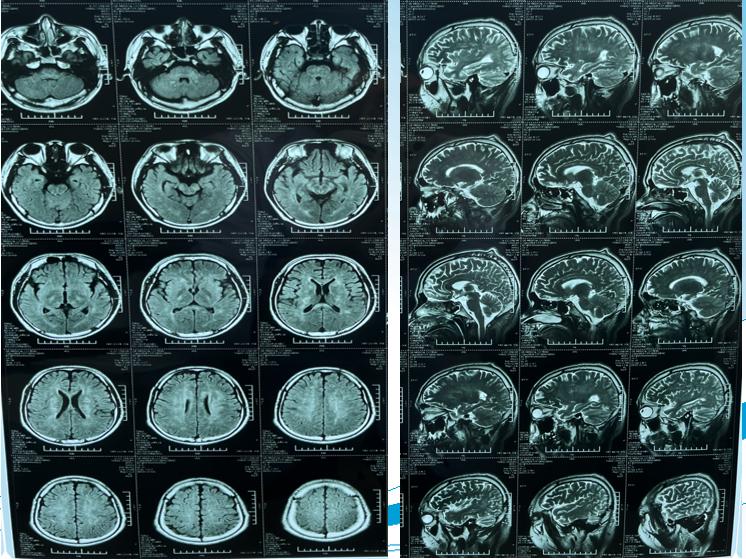

根据结脑中心副主任医师李欢介绍,患者在入院时,体温持续在38-39℃之间,双下肢瘫痪。科室组织会诊后发现,与常见的结核性脑膜炎相比,该患者临床症状有特别之处,而且抗结核治疗后效果不佳,随后便对患者进行了颅内疾病的全面筛查。最终确定为自身免疫性胶质纤维酸性蛋白星形胶质细胞病。李欢表示,这种疾病是一种可治的中枢神经系统自身免疫性炎性疾病,是一类较罕见的病例,也是传染病医院收治的首例病例。